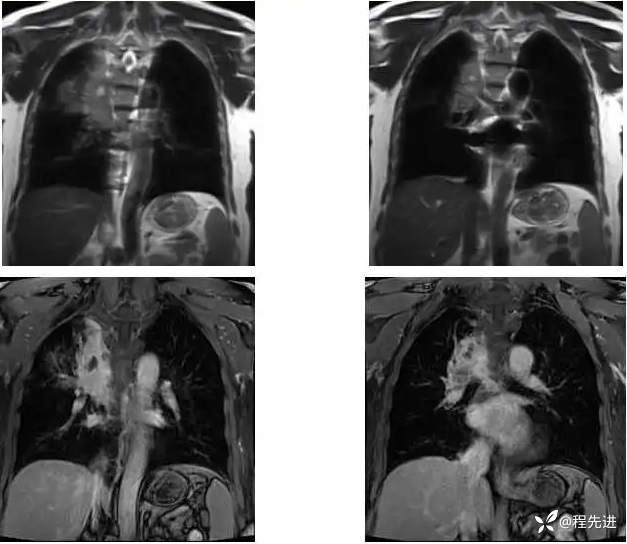

MR平扫+增强:

T2压脂:

T2;

T1压脂:

T1增强;